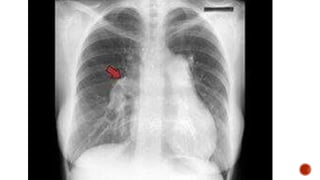

SIGNOS DE CRECIMIENTO DE CAVIDADES DERECHAS.

 AUMENTO DE ESTRUCTURAS VASCULARES.

 DILATACION DEL VENTRICULO DERECHO.

 AUMENTO DEL ICT.

 OBLITERACION DEL ESPACIO RETROESTERNAL.

SIGNOS DE CRECIMIENTODE CAVIDADES DERECHAS.

 AUMENTO DEESTRUCTURAS VASCULARES.  DILATACION DEL VENTRICULO DERECHO.  AUMENTO DEL ICT.  OBLITERACION DEL ESPACIO RETROESTERNAL. SENSIBILIDAD 97% ESPECIFICIDAD 99%